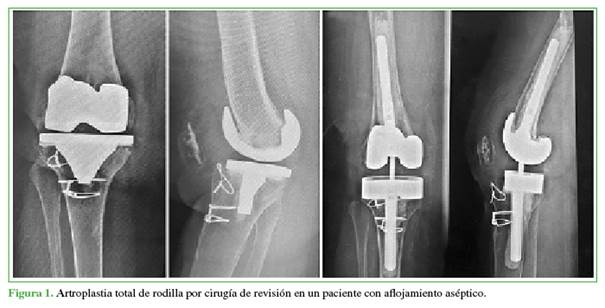

No se hallaron diferencias estadísticamente significativas en la cirugía (primaria o revisión) y el tiempo de seguimiento entre los subgrupos (Figuras 1 y 2).

El implante fue cementado en fémur y tibia; en algunas ocasiones, se utilizaron vástagos y cuñas según necesidad. Se realizaron 51 ATR con implante TC3; 43 de estos pacientes estaban aptos para la evaluación (3 perdidos en el seguimiento, 1 muerto, 4 no caminaban más debido a otras enfermedades). El 79% eran mujeres y el 21%, hombres, y la edad promedio en el momento de la evaluación era de 73.7 años (rango 54-90). El seguimiento osciló entre 6 meses y 7 años (promedio 27 meses). El 63% de las cirugías eran primarias (osteosíntesis u osteotomía previa); y el 37%, de recambios (asépticos e infectados).

Los implantes semiconstreñidos ofrecen varios elementos para aumentar la estabilidad y balancear las brechas en flexión y extensión,8 como componentes femorales y tibiales más grandes, vástagos en tibia y fémur, cuñas y steps metafisarios de tibia para complementar defectos óseos, cajón más profundo e insertos más grandes.9